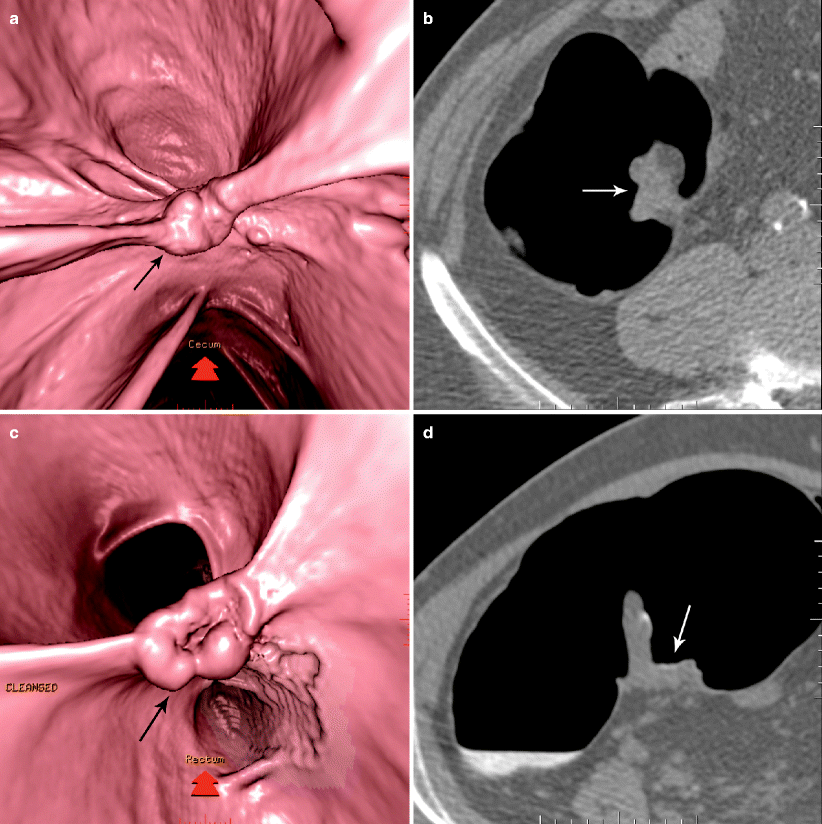

(a) Medially placed ileocecal valve (arrow). (b) Dilated, twisted cecum What Causes The Ileocecal Valve To Close Web the main function of the icv is to open and close periodically in order to let food move through the digestive tract. Web the ileocecal valve (ileal papilla, ileocaecal valve, tulp's valve, tulpius valve, bauhin's valve, ileocecal eminence, valve of. Basic dysfunction of the ileocecal valve can cause backflow of cecal contents into the ileum. Lower right part of. What Causes The Ileocecal Valve To Close.